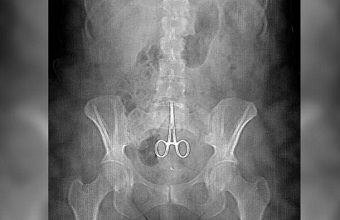

Hombre tuvo por más de 10 años una tijera quirúrgica dentro de su cuerpo

BARAHONA.- Fue ingresado en el hospital Jaime Mota de esta ciudad un hombre al que se le detectó una tijera o pinza quirúrgica incrustada dentro del estómago y la columna, que se la dejaron los médicos en una de dos operaciones que le hicieron en el mismo centro asistencial hace más de una década.

BARAHONA.- Fue ingresado en el hospital Jaime Mota de esta ciudad un hombre al que se le detectó una tijera o pinza quirúrgica incrustada dentro del estómago y la columna, que se la dejaron los médicos en una de dos operaciones que le hicieron en el mismo centro asistencial hace más de una década.

Se trata de Dionisio Guevara Ruiz, cuya primera intervención quirúrgica le fue hecha hace nueve años y la segunda tres años después.

En esta ocasión Guevara era objeto de fuertes dolores en su columna, por lo que procedió a consultar con un ortopeda, quién le detectó el objeto tras hacerle una radiografía.

Inmediatamente este fue preparado y enviado a cirugía para ser operado por tercera ocasión, pero esta vez para extraerle la tijera que tiene incrustada entre el estómago y la columna.

«Este fue operado en dos ocasiones en este mismo hospital hace doce años, en una de las cuales, estamos seguros, que se le dejaron el instrumento quirúrgico en su cuerpo», dijeron parientes del afectado.